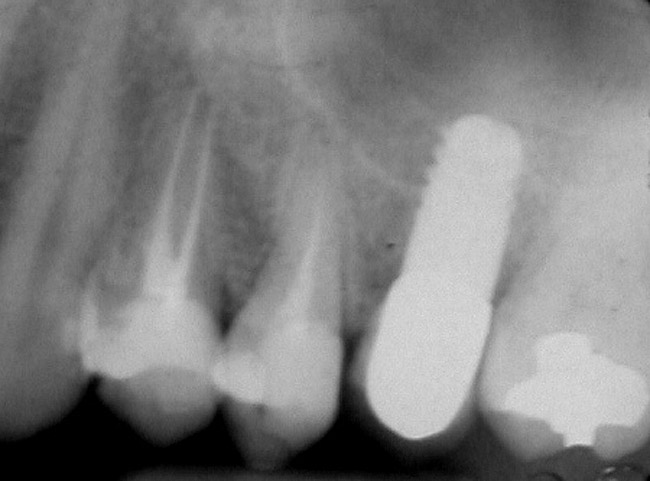

A 55-year-old male was referred for implant placement and prosthetic rehabilitation in the area of tooth No. 15. The tooth had been extracted 4 years prior. The radiograph revealed inadequate bone height for implant positioning (Figure 6). It was decided to insert an implant that was 11.5 mm in length and 3.75 mm in diameter, performing a slight osteotomic maxillary sinus lift. A heterologous bone graft also was planned to obtain a larger sinus lift.

A full-thickness mucoperiosteal flap was raised, and alternating osteotomes were used to prepare the implant site. After achieving a length of 7 mm (Figure 7A and Figure 7B), heterologous bone graft was implanted and the osteotome sequence was repeated. The implant showed primary stability.

Figure 6  Preoperative radiograph of the area around tooth No. 15.

Figure 6

Figure 8  At 4 months after treatment, the radiograph revealed the presence of a bone layer surrounding the implant.

Figure 8